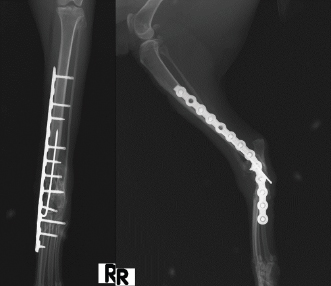

An 18-month-old female stray European cat was referred to the Veterinary Teaching Hospital of the University of Camerino, Italy. Anamnestic data reported a distal tibial epiphyseal sliding fracture (SH1) of the right hind limb inadequately treated 8 months prior with an intramedullary pin by colleagues and consequent chronic tarsocrural instability. Gait evaluation showed a non-weight bearing lameness (grade 4/5) of the right hind limb. An orthopedic examination revealed severe pain during the manipulation of the right tarsus, with bone crackling during stressed manipulation elicited by tibiotarsal joint laxity. Mediolateral and craniocaudal projections of the right tarsus showed failure of the fracture implant (intramedullary pin) caused by an inadequate choice of the apparatus and an incorrect osteosynthesis technique, with a caudomedial displacement of the right distal tibial epiphysis and a moderate process of bone remodeling and resorption (Fig. 1). The patient underwent pantarsal arthrodesis for the recovery of limb functionality. The anesthetic protocol included premedication with 3 μg/kg of dexmedetomidine (Dexdomitor 0.5 mg/ml; Orion Corporation, Finland), 0.3 mg/kg of methadone (Semfortan 10 mg/ml; Dechra, Italy), and 3 mg/kg of ketamine (Ketavet 100; Intervet Productions s.r.l., Italy) administered intramuscularly (IM). General anesthesia was induced with 4 mg/kg of propofol (Fresenius Kabi, Isola della Scala, Italy) administered intravenously (IV) and maintained with oxygen and isoflurane. When a good anesthesia plan was achieved, the femoral–sciatic nerve block was carried out with 0.2 ml/kg of lidocaine (Xylocaine 2%; Zidus Cadila, India). The affected limb and the contralateral foreleg were clipped, and a 4% chlorhexidine gluconate detergent was used for the preliminary preparation of the surgical sites, with a minimum contact time of 5 minutes. The patient was positioned in right lateral recumbency, with the affected limb toward the operating table and the contralateral limb fixed in the abduction position. Cefazolin (Cefazoline Teva; Teva s.r.l., Italy) was administered IV (22 mg/kg) approximately 30 minutes before the skin incision. Under complete aseptic precautions, the craniomedial approach was carried out to expose the tarsal joint. A skin incision, the same length as the plate, was made on the caudomedial aspect of the distal tibia and the craniomedial aspect of the tarsus and proximal metatarsus. The intramedullary pin was removed and sent to the laboratory for bacteriological examination. The tarsocrural, intertarsal, and tarsometatarsal joints were exposed, and the articular cartilage was removed with a high-speed burr. The autologous bone graft was collected from the cancellous bone of the contralateral humerus and was subsequently inserted into the joint spaces. After joint reduction, pantarsal arthrodesis was performed. A 1.2-mm Kirschner wire was driven through the calcaneus into the tibia, and a Compact UniLock 2.0 mandible locking plate (DePuy Synthes, Oberdorf, Switzerland) of 1.5-mm thickness was contoured to achieve the functional angle of tarsus extension and was positioned on the medial surface of the tarsus (Fig. 2). The plate was fixed with ten 2.0 mm locking screws and a cortical screw. The soft tissues were sutured by planes using a USP 3/0 absorbable monofilament thread. No tension at the suture lines was observed. The surgery lasted for 63 minutes. At the end of the surgery, an X-ray examination (Fig. 3) showed a good apposition of the fracture, with a slight internal rotation of the calcaneus; the apparatus seemed adequate, with a total plate screw density (PSD) of 0.85. The joint was fixed at 137° in extension. After radiographic examination, a soft padded bandage was applied for 14 days, which was renewed weekly. As needed, 0.3 mg/kg of methadone (Semfortan 10 mg/ml; Dechra, Italy) was administered IM for 24 hours postoperatively. Anti-inflammatory therapy (meloxicam 0.05 mg/kg; Metacam 40 mg/ml; Boehringer Ingelheim Vetmedica, Germany) and ranitidine (2 mg/kg; Zantadine 30 mg/ml; Ceva s.p.a., Italy) IV were administered on an inpatient basis. The first orthopedic evaluation, the first day after surgery, showed an improvement in gait (grade 2/5 of lameness on walk). The cat was discharged from the hospital after 3 days with a prescription of anti-inflammatory and analgesic therapy. The head of the cat shelter was instructed to subject the cat to cage rest for 30 days. At the first follow-up, 7 days after surgery, the soft padded bandage was renewed, and the cat showed a steady improvement in gait. Fourteen days after surgery, the soft bandage was removed; the orthopedic examination showed mild improvement in gait, although second-degree lameness and an extended tarsal and flexed stifle gait persisted because of the arthrodesis procedure. No swelling or dehiscence at the surgical site or skin tension under the plate was observed; the suture was removed, and the cat was discharged with light exercise on a larger cage recommendation for the remaining 15 days. One month after surgery, at the orthopedic evaluation, the head of the cat shelter reported a slight worsening of lameness after a sharp jump had occurred 7 days prior. The patient showed good limb function, with a slight worsening of gait during the trot, and the radiographic evaluation showed good bone activity, with 50%–66% of the joint fusion and fracture healed, although a metatarsal stress fracture was revealed (Fig. 4). Four months after surgery, radiographs revealed stable implants and an almost complete fusion of the joints (Fig. 5). The surgical wound site, 30 and 120 days after surgery, healed very well, with an efficient aesthetic result of the limb, even with a slight loss of skin elasticity, which occurs naturally after surgery. The patient never showed discomfort at the implant site, even though the plate was very superficial and palpable under the thin skin (Fig. 6). Moderate free activity with gradual introduction to freedom in the feline colony was prescribed.

Fig. 1. Craniocaudal and mediolateral radiographs of right tibia and tarsus showing an inveterate articular fracture of right distal tibial epiphysis with cranial displacement, previously treated with an intramedullary pin (see arrows). The pin does not engage the proximal portion of the tibia and runs for almost its entire length in the caudal portion of the leg.